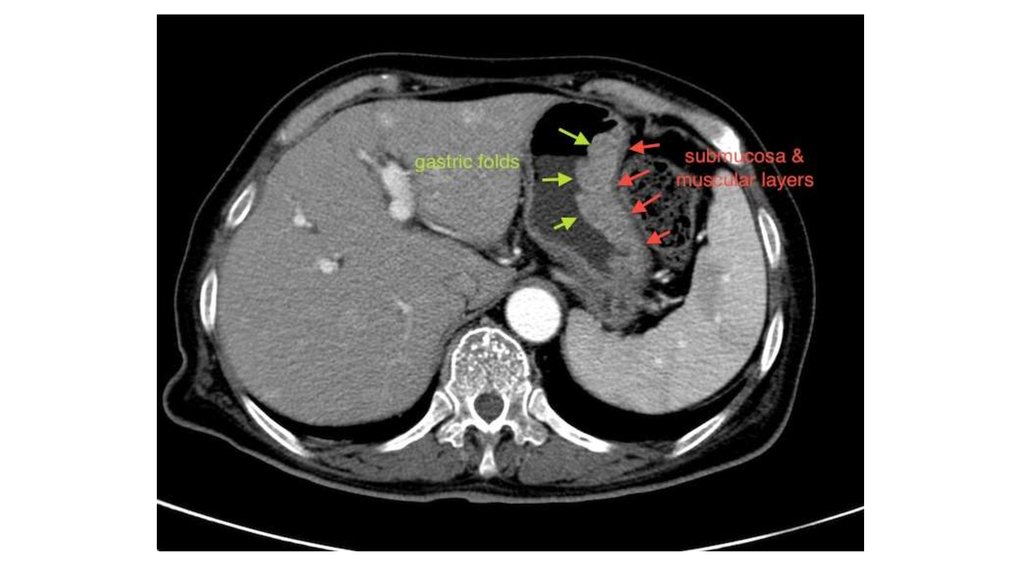

9. Рентгенологические признаки

резко утолщенные складки слизистой желудка

межскладочные промежутки при этом расширены и

отечны

стенки желудка эластичны, перистальтика в норме.

Различают распространенную и ограниченную формы

аномалии. При ограниченной форме болезни Менетрие

обнаруживают скопление толстых извилистых складок,

которые значительно выступают в просвет желудка и

представляют собой дефект наполнения неправильной

формы, состоящий из «подушкообразных» образований.

Локализация - большая кривизна напротив угла желудка.

При распространенной форме - в своде, теле и синусе

желудка. При этом в антральном отделе выявляют

нормальные складки.

10. Эндоскопические признаки

утолщение складок слизистой оболочки, которые

напоминают извилины мозга или булыжную мостовую

на вид складки бледные, отечные, иногда

гиперемированые

слизистая желудка в верхушках складок часто покрыта

эрозиями

Методика дозированного раздувания желудка воздухом

при эндоскопическом исследовании позволяет выявить

гигантские складки, которые не расправляются при

давлении в желудке более 15 мм рт. ст.